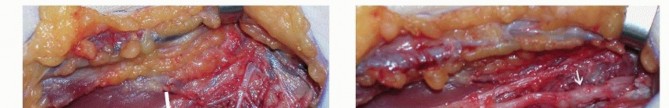

The surgical approach to a neuroma-in-continuity demands meticulous, atraumatic microsurgical technique. The fundamental principle is to initiate the dissection in pristine, unscarred anatomical planes both proximal and distal to the zone of injury. By identifying the normal nerve trunk first, the surgeon can trace it toward the epicenter of the neuroma, carefully dissecting it free from the surrounding fibrotic bed. This external neurolysis involves incising the overlying fascia and meticulously dividing the compressive epineurial scar tissue, freeing the nerve circumferentially while strictly preserving the longitudinal vasa nervorum.

Once the neuroma is completely mobilized, the most critical phase of the operation commences: the acquisition of Intraoperative Nerve Action Potentials (NAPs). This technique, pioneered by Kline, is the definitive arbiter of whether a neuroma-in-continuity requires resection or merely neurolysis. The nerve is suspended on bipolar stimulating electrodes proximally and recording electrodes distally across the neuroma. A supramaximal stimulus is applied. If a reproducible NAP is recorded distally, it definitively proves that a functionally significant number of axons (typically >3000-4000 myelinated fibers) have successfully traversed the scar tissue. In this scenario, external neurolysis alone is sufficient, and the nerve is left intact.

Conversely, the absence of a transmitted NAP across the neuroma at the 3-to-4-month mark indicates a Sunderland IV injury. The dense intraneural scar is an insurmountable barrier to regeneration. The surgeon must then proceed with resection of the neuroma back to healthy, pouting fascicles proximally and distally, followed by reconstruction. However, the clinical reality is rarely binary. Often, the nerve exhibits a mixed injury pattern, where some fascicles conduct a NAP while others are completely fibrosed. This necessitates the highly advanced technique of internal neurolysis and split repair.

During a split repair, the external epineurium is longitudinally incised under high microscopic magnification. Using micro-scissors and jewelers' forceps, the surgeon delicately dissects the internal epineurium, separating the individual fascicular groups. Each fascicular group is then independently interrogated with the NAP electrodes.

The functioning fascicles (those conducting a NAP) are carefully neurolysed and preserved. The non-functioning, fibrotic fascicular groups are sharply resected using a diamond knife or micro-scissors until healthy, unscarred axonal tissue is visualized.

This selective resection creates a segmental defect specifically in the non-viable portion of the nerve.